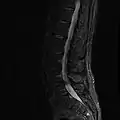

MRI lumbar spine with degeneration (sagittal T2 FRFSE)

MRI lumbar spine with degeneration (sagittal T1 FSE)

MRI lumbar spine with degeneration (sagittal FAST STIR)- MRI lumbar spine pre-hemilaminectomy (sagittal T2 FRFSE)